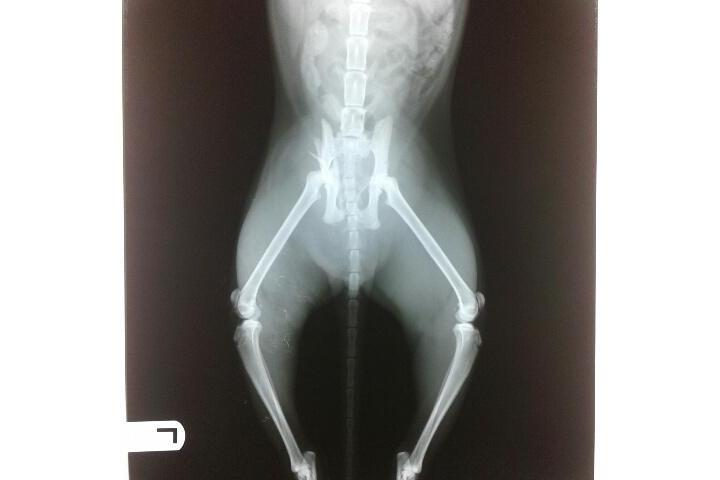

PANDORA: ya lleva 15 días recuperándose de su fractura de la cadera. Parece que la cosa va bien, menos su caracter que se ha vuelto más arisca (quien no lo estaria encerrada 24H sin poder moverse?). No come mucho aunque no tenga que gastar mucha energía. A ver si dentro de 2 semanas ya esta soldada la fractura y podemos mejorar su calidad de vida.

Si os acordais hace casi 1 mes y medio (mediados de abril) me encontre con una gata de una de mis colonias con la cadera fracturada. Pues despues de estar encerrada desde entonces para que se recupere, hoy a recobrado su libertad. A las 6.30am, la he soltado en la colonia. No esta del todo perfecta, le ha quedado cojera (el pie no lo apoya bien) pero anda y se sube a las paredes como buena gata callejera. Espero que con un poco de tiempo, el pie se ponga bien (por desgracia no tenia mucho espacio para andar ya que muy simpatica no lo es :) ) pero al menos una buena cosa hecha y ahora podré verla cada mañana con sus compañeros a la hora de la comida. A valido la pena, ya que da mucha alegría ver que ha salido adelante y a tenido la oportunidad de estar cuidada, cosa que no todos los gatos callejeros de L'Escala tienen.

Esta mañana me he encontrado a la Negrita, gata operada de una de mis colonias cobijada al interior de la caseta que tienen y maullando mucho. Vi que no estaba bien, no se movia y no venia a comer. No llevaba nada, sali corriendo de vuelta a casa para coger transportin y red, pero no llegaba al fondo de la caseta y se me acababa el tiempo. Al final Conxita mi compañera y presidenta con su marido, y despues de alguna peripecia pudieron cojerla. La he llevado esta tarde a radiografias: tiene una fractura a nivel de la cadera. Algun golpe de coche (?)... pero parece que con reposo se suelen recuperar. Ahora la tengo en casa, a ver si no tiene nada malo por dentro.... a ver si con reposo mejora y sobretodo se "socializa" un poco más. Me conoce, pero nunca la he podido tocar :) . A cruzar los dedos.